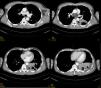

Durante el ingreso se realiza tomografía axial computarizada (TAC) toraco-abdominal y boncoscopia. En la TAC se evidencia la presencia de una consolidación parenquimatosa con aireación periférica y broncograma que afecta a segmentos posteriores de lóbulo inferior izquierdo (LII). Sin adenomegalias mediastínicas ni nódulos ni masas parenquimatosas pulmonares (fig. 1).